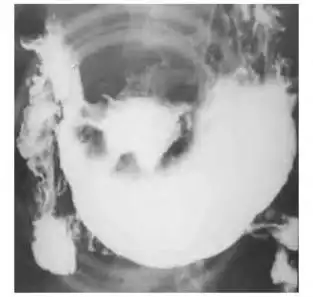

图3-41 胃溃疡型癌,钡餐检查,见腔外不规则龛影,有"环堤"及"指压迹"征

溃疡型:龛影大多成多角形;周围有清楚的环堤;周围皱襞中断,末段呈杵状